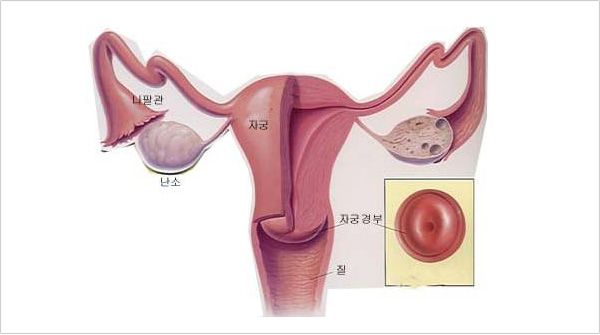

�ڱð�� Ȯ�� �Կ��˻�

�ֽ� ���� �ػ� ������ ���� �ڱð�κ����� �߰��ϰ� �����˻���� ������ ����Դϴ�. ���� ��Ȯ�� ����� �˱� ���ؼ��� �ڱ� ����� ���Ҹ� Ȯ�� �����ϴ� ��Ȯ��� �˻縦 �ϰ� �˴ϴ�. ���� �δ���� ������ ������ �� ������ ������ �˻�� ����� 98%������ ��Ȯ���� ��Ÿ���ϴ�.

�ֽ� ���� �ػ� ������ ���� �ڱð�κ����� �߰��ϰ� �����˻���� ������ ����Դϴ�. ���� ��Ȯ�� ����� �˱� ���ؼ��� �ڱ� ����� ���Ҹ� Ȯ�� �����ϴ� ��Ȯ��� �˻縦 �ϰ� �˴ϴ�. ���� �δ���� ������ ������ �� ������ ������ �˻�� ����� 98%������ ��Ȯ���� ��Ÿ���ϴ�.

�ڱð�ο� ���� ��θ� �ʻ����� ó���� �� �ʻ��� ������ ���̴� ��Ҹ� Ȱ���� �� ������ ���� �ǵ��ڰ� �м��ϴ� ������ �ǵ��ڴ� ����� �Ⱓ�� ������ ���� ������ ���ΰ� ������ �� Colposcopy ������ �������Դϴ�.

| �ڱð�� Ȯ�� �Կ��˻��� ���� |